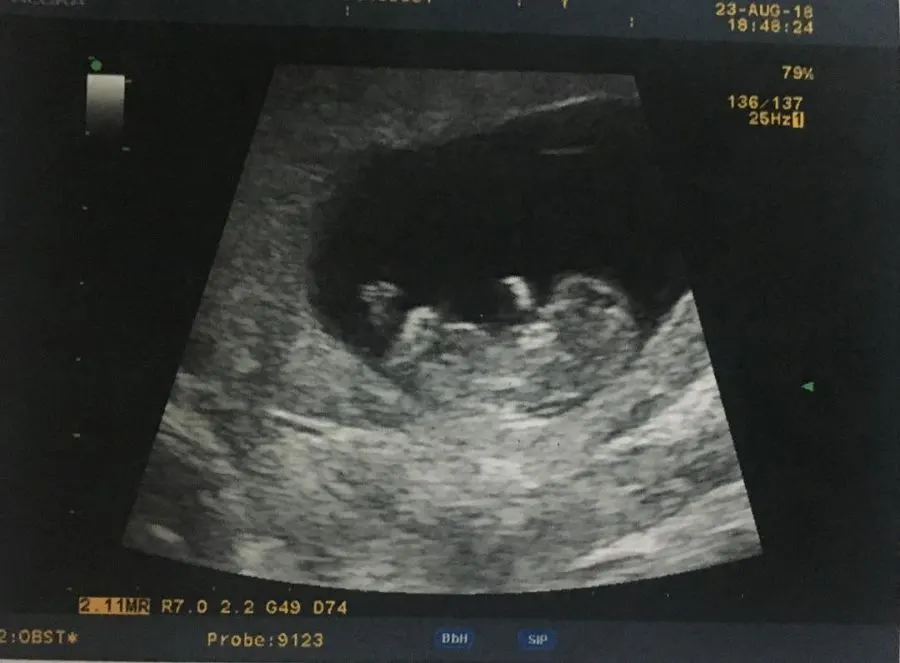

หลังจากแต่งงานไปได้ไม่นาน ก็กลายเป็นคุณแม่ไปซะแล้วล่ะค่ะ สำหรับ "หนูเล็ก ก่อนบ่าย" หรือ ภัทราวดี ปิ่นทอง ที่ตอนนี้เธอก็อุ้มท้องลูกน้อยกว่า 5 เดือนแล้ว คุณแม่ก็ตื่นเต้นเป็นธรรมดา

ล่าสุด หนูเล็กก็เผยโมเม้นท์สุดตื่นเต้นของคนเป็นแม่ เมื่อลูกน้อยในท้องดิ้นแรงอย่างชัดเจน โดยเธอได้ออกมาเผยคลิปวิดิโอลงไอจี พร้อมแคปชั่นว่า...

"5 เดือน ลูกบ่าวแม่ดิ้นแรงขึ้น จนแม่สะดุ้งตกใจทุกที. พอหนูดิ้นหัวใจแม่จะเต้นเร็ว บางทีแอบเหนื่อยนานอยู่. #ก่าก๊าน้อย #พี่win"

ลูกดิ้นแรง

5 เดือนแล้ว